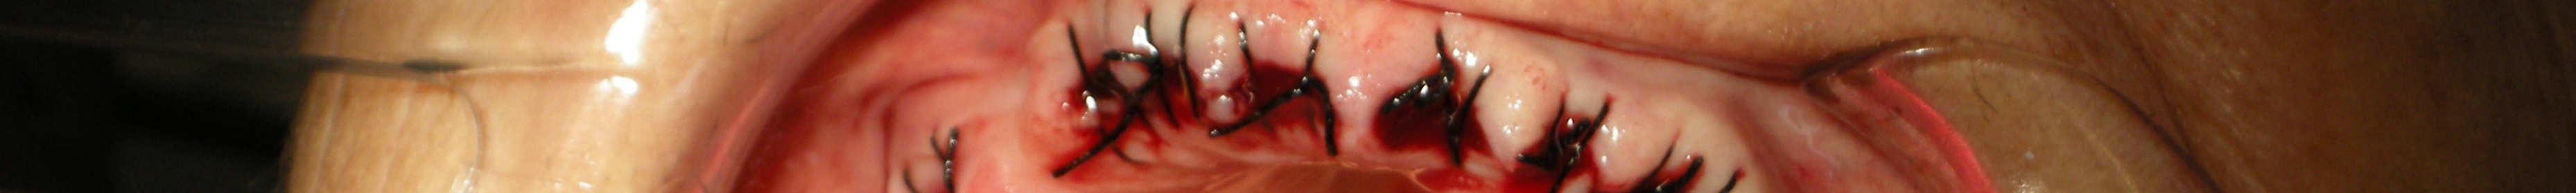

Implantology

Dr. Valter Pirazzoli